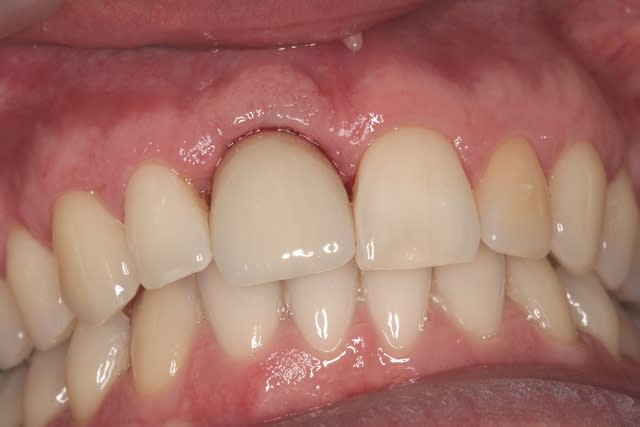

le hasard fait parfois bien les choses...patient revu ce matin pour une "bricole" sur une restauration postérieure...

il est intéressant de voir la maturation des tissus mous...et en plus VS des différences au niveau de l'hygiène, pas mal secteur 2 mais perfectible secteur 1...

ici on est à 3 mois post pose prothèses d'usage...la photo, prise un peu décalée, donne l'impression d'une différence de hauteur des collets, mais il n'en est rien (ou alors très peu...)

quand même content du résultat...;-) même si j'ai (lourdement)insisté pour que l'hygiène soit un peu mieux suivie...